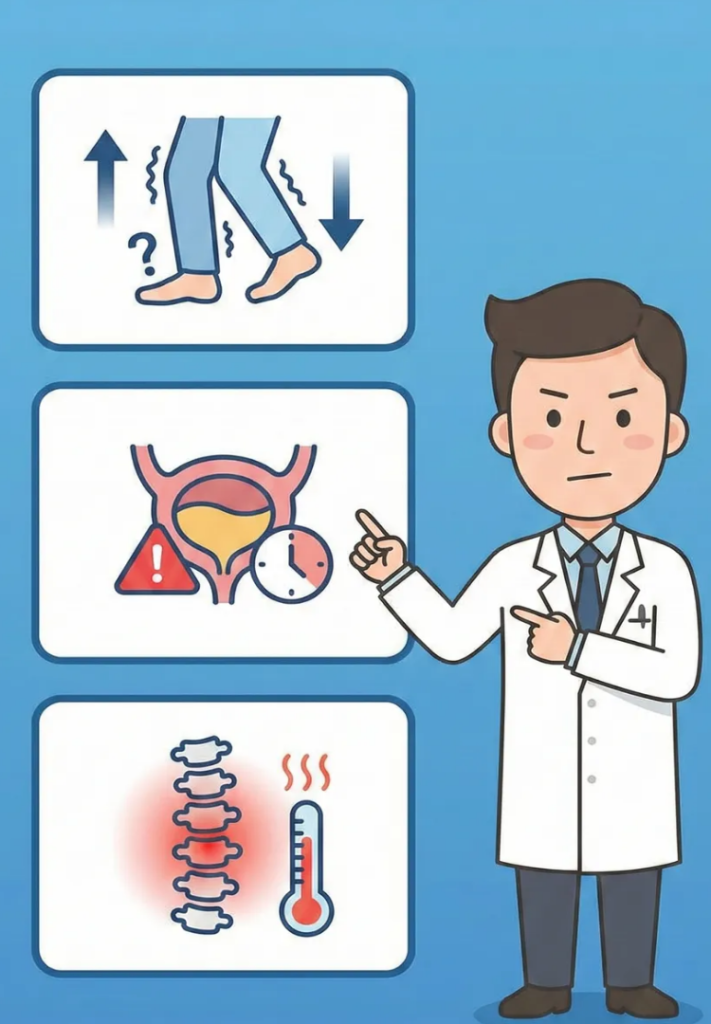

3. 참으면 안 되는 허리 통증의 위험 신호

대부분의 허리 통증은 비수술적 치료로 호전되지만, 절대 방치해서는 안 되는 위험한 신호들이 있습니다.

이런 신호를 무시하고 단순히 주사치료만 한다면 돌이킬 수 없는 결과를 낳을 수 있습니다.

아래 증상이 나타난다면 치료의 골든타임을 놓치지 않도록 즉시 병원을 찾아야 합니다.

- 다리에 힘이 빠질 때: 까치발을 서거나 발뒤꿈치로 걷는 것이 어려워지고, 계단을 오르내릴 때 다리가 풀리는 느낌이 든다면 심각한 신경 손상을 의미할 수 있습니다. 특히 힘이 점점 더 빠진다면 즉시 응급실을 내원 해야 합니다

- 대소변 장애가 생겼을 때: 소변이나 대변을 보기가 힘들거나, 자신도 모르게 실수를 하게 된다면 응급 상황(마미 증후군)일 수 있으므로 즉시 응급실이나 전문 병원을 찾아야 합니다.

- 열이 나면서 허리가 아플 때: 척추에 염증이나 감염이 생겼을 가능성이 있습니다.

- 넘어져서 허리가 아플 때: 외상 이후 발생한 요통은 반드시 골절을 먼저 감별해야 하며 단순 방사선 검사를 먼저 시행해야 합니다.